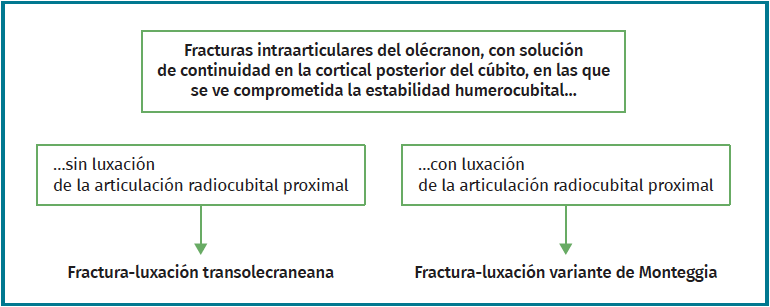

A pesar de que no existe un consenso en relación con la clasificación de las fracturas-luxaciones del codo y ateniéndonos al concepto fractura-luxación transolecraneana, en estas lesiones debe existir una fractura intraarticular del olécranon, con solución de continuidad en la cortical posterior del cúbito, en la que se ve comprometida la estabilidad humerocubital. Si no existe una luxación de la articulación radiocubital proximal, el término adecuado es “fractura-luxación transolecraneana” y, si se asocia una luxación de la articulación radiocubital proximal, “fractura-luxación variante de Monteggia” (Figura 1). Los estudios radiológicos no siempre permiten diferenciar claramente los patrones de fractura por lo que la tomografía axial computarizada (TAC) y especialmente las reconstrucciones tridimensionales son imprescindibles para su diagnóstico.